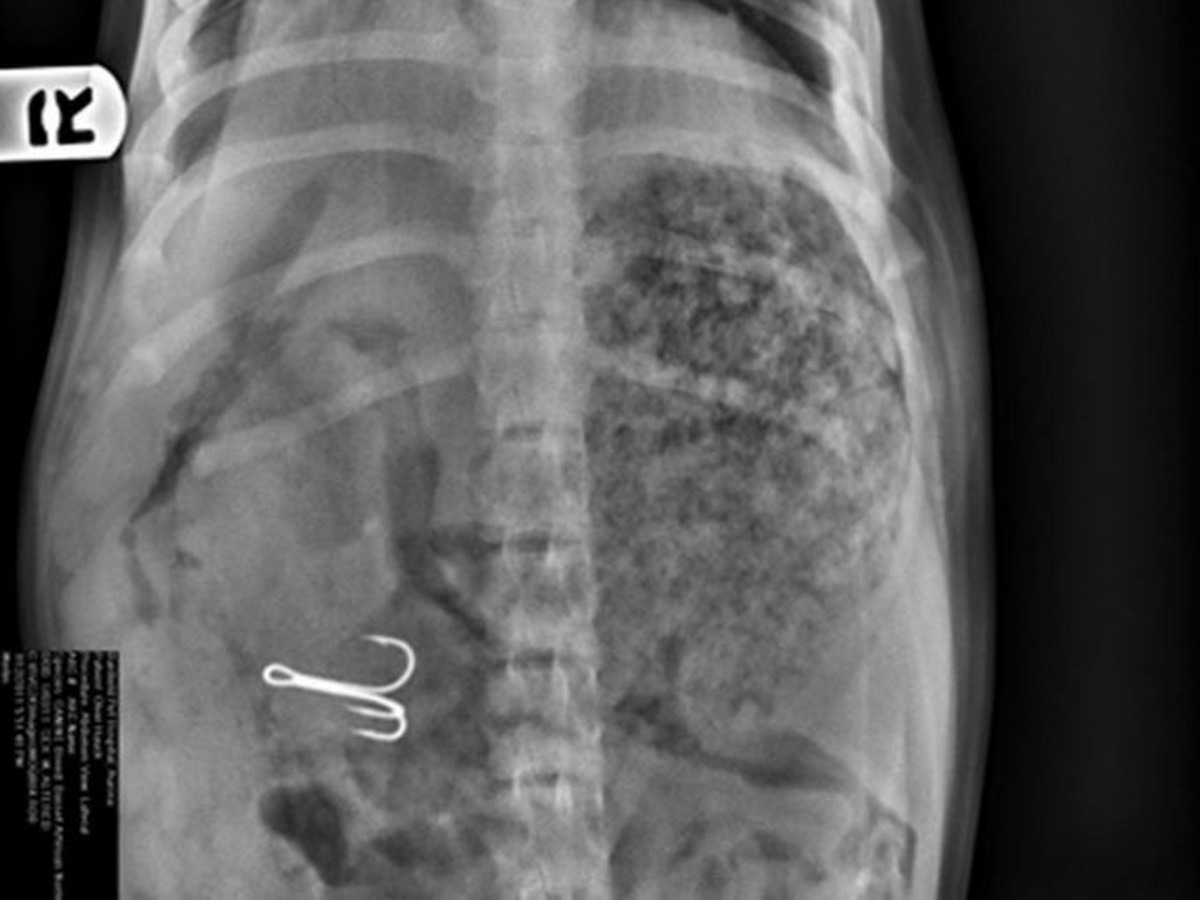

令人驚訝的當然不止上述的小青蛙,來自佛羅里達州一隻6歲狗狗馬利(Marley)亦成為是次比賽的焦點!事情的緣由是狗狗看見主人放下插滿蔬菜及肉肉的串燒燒烤針後,竟趁著主人走開時吃下其中一支針!當主人回頭看時才驚覺Marley已將燒烤針吞下。負責診治狗狗的獸醫高斯曼(Tim Gossman)表示,主人起初都不敢相信毛孩吞下了燒烤針,「後來我做了X光檢查向他證明,最後真的看到燒烤針清晰地出現在狗狗的胃內。」